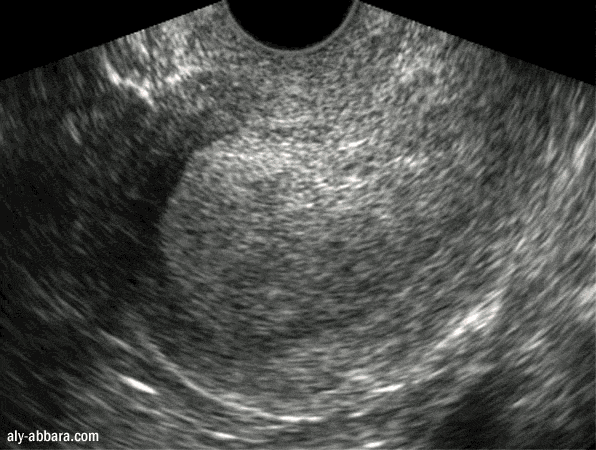

Hyperplasie de l'endomètre chez une patiente atteinte

d'une dystrophie ovarienne

Endomètre de 35 mm d'épaisseur